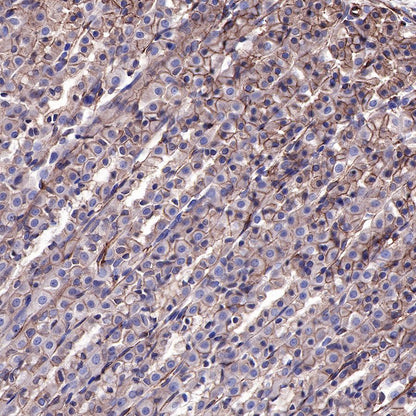

IHC shows positive staining in paraffin-embedded human hepatocellular carcinoma. Anti-EGFR antibody was used at 1/2000 dilution, followed by a HRP Polymer for Mouse & Rabbit IgG (ready to use). Counterstained with hematoxylin. Heat mediated antigen retrieval with Tris/EDTA buffer pH9.0 was performed before commencing with IHC staining protocol.